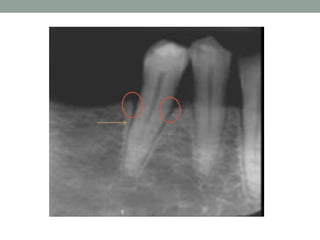

Radiographic signs of OT

• Increased width of PDL space

(funnel-shaped coronally).

• Thickening of lamina dura.

• Vertical or angular bone loss.

• Radiolucency in furcation areas.

• Root resorption